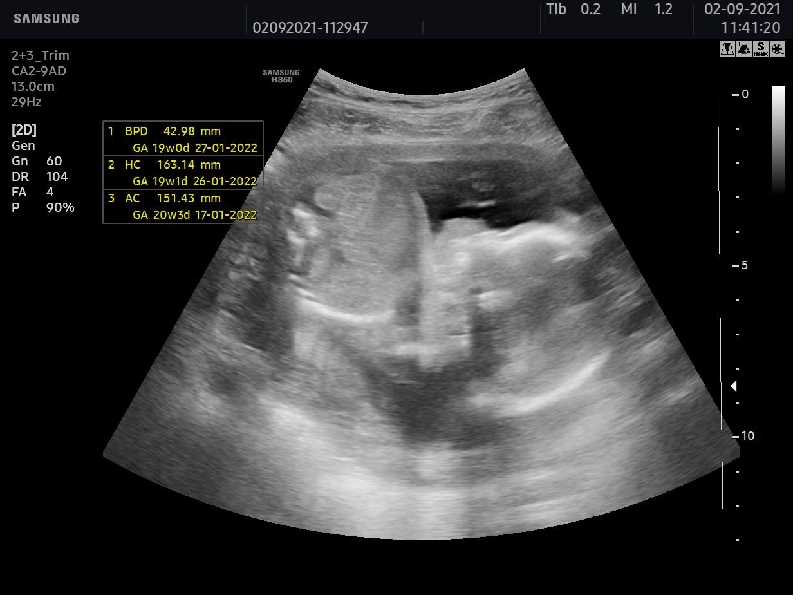

Dobrý den jsem dnes 19+3tt, včera jsem byla na prohlídce u svého dr. Který mi sdělil pohlaví miminka ale tak trošku nejistě. Prý vypadá to na holku myslíte že mám naději ještě že by se z toho mohl vyklubat chlapeček. Podotýkám že nás bývalý pan dr. Náš posílal na velký utz na fifejdy ke specialistovi. Ale můj nový dr. To dělá sám a utz nemá moc kvalitní, přikládám foto. Stalo se vám některé ze by v pozdějším stádiu těhotenství změnil názor na pohlaví? Předem děkuji za odpovědi

@sherryel vám to jde krásně vidět jenže mne doktor řekl na minulé kontrole že mne bude vyšetřovat 25min no a včera když sem tam přišla byla jsem objednaná na 10:15 vzal mne až za hodinu a utz tvrval že vsim všudy asi 10min a ještě k tomu sem tlna tom utz nic nevidela jak to rychle prejizdel poznala jsem jen srdíčko a ruce nevím zda tomu věřit mám foto s třetího měsíce a tam mi přijde že tam ten pinda je no je pravda že v těch utz se moc dobře nevyznám. Co myslíte?

@andysek1235 : u nás jsou tam viditelné dva ovalky a je to na 90% holka. U kluka byl ult. Hodně průkazný ( úplný pornoherec ) ...